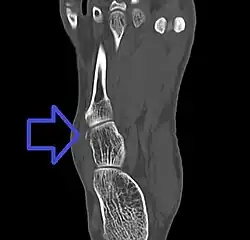

A cuboid fracture is a fracture of the cuboid bone of the foot. Diagnosis is by X-ray imaging, magnetic resonance imaging, or bone scan.[1] Treatment may be conservative or involve surgery, depending on the type of fracture.[1] They are rare.[1]

If the cuboid bone is broken, then it is common for other bones in the foot to be broken or dislocated as well.[2] Cuboid fractures are associated with Lisfranc injuries.[2]